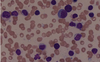

A 71-year-old man comes to the clinic because of headaches and blurry vision for the past two months. He also states that any time he grabs food out of the freezer, his fingers turn white for awhile and then blue before becoming painful and the color returning to normal. His temperature is 38.1°C (100.6°F), pulse is 78/min, respirations are 14/min, and blood pressure is 138/84 mm Hg. Physical examination shows generalized lymphadenopathy. Neurologic testing shows decreased visual acuitybilaterally. He denies pain in his extremities or back. Laboratory studies show a normal serum calciumand creatinine. Serum protein electrophoresis shows an M-spike consisting of IgM. Bone marrow aspirate (shown below) shows multiple atypical lymphocytes. Which of the following is the most likely diagnosis?

Waldenstrom macroglobulinemia

Waldenstrom macroglobulinemia is a B-cell lymphoma characterized by the production of monoclonal IgM, which differentiates it from multiple myeloma. Symptoms are caused by hyperviscosity of the blood, manifesting as blurred vision, neurologic deficits, generalized lymphadenopathy, and Raynaud phenomenon. Diagnosis includes serum protein electrophoresis with an M spike due to IgM.